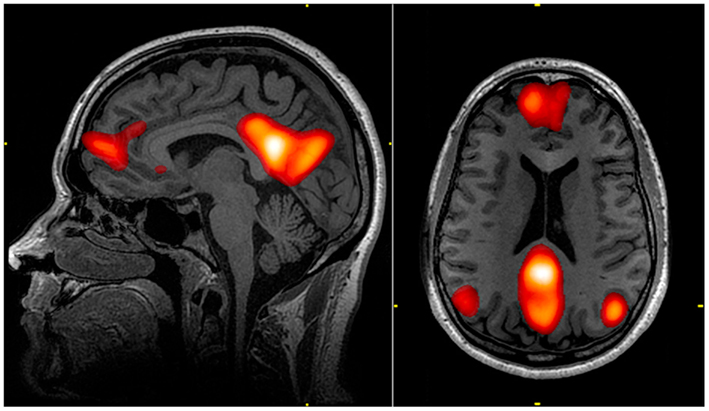

Waarom kan de één na een drukke dag direct de knop omzetten, terwijl de ander nog urenlang ligt te piekeren? Dit heeft alles te maken met het Default Mode Network in ons brein. Dit netwerk wordt actief zodra we niet gefocust zijn op een specifieke taak. Bij vrouwen blijft dit systeem in ruststand vaak actiever, wat leidt tot een constante stroom van reflectie, sociale analyse en planning.

Mannen lijken dit netwerk daarentegen makkelijker te kunnen “parkeren”. Hierdoor kunnen zij vaak moeiteloos ontspannen zonder gehinderd te worden door een interne lijst met onafgeronde zaken. Dit contrast zorgt voor de klassieke situatie waarbij de één nog volop piekert over de logistiek van morgen, terwijl de ander al vredig ligt te slapen.

Het is belangrijk om te erkennen dat deze “interne ruis” geen onwil is. Voor de één is rusten een bewuste inspanning waarbij het brein actief tot bedaren moet worden gebracht, terwijl het voor de ander een natuurlijke staat van zijn is. Begrip voor dit neurologische verschil kan veel onbegrip over elkaars ontspanningsrituelen wegnemen.